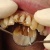

Vahel on hammastel tumenenud fissuurid ja tumedad peetunud kaariese laigud, neid tõesti pole suurt mõtet puurida. Hammas ...